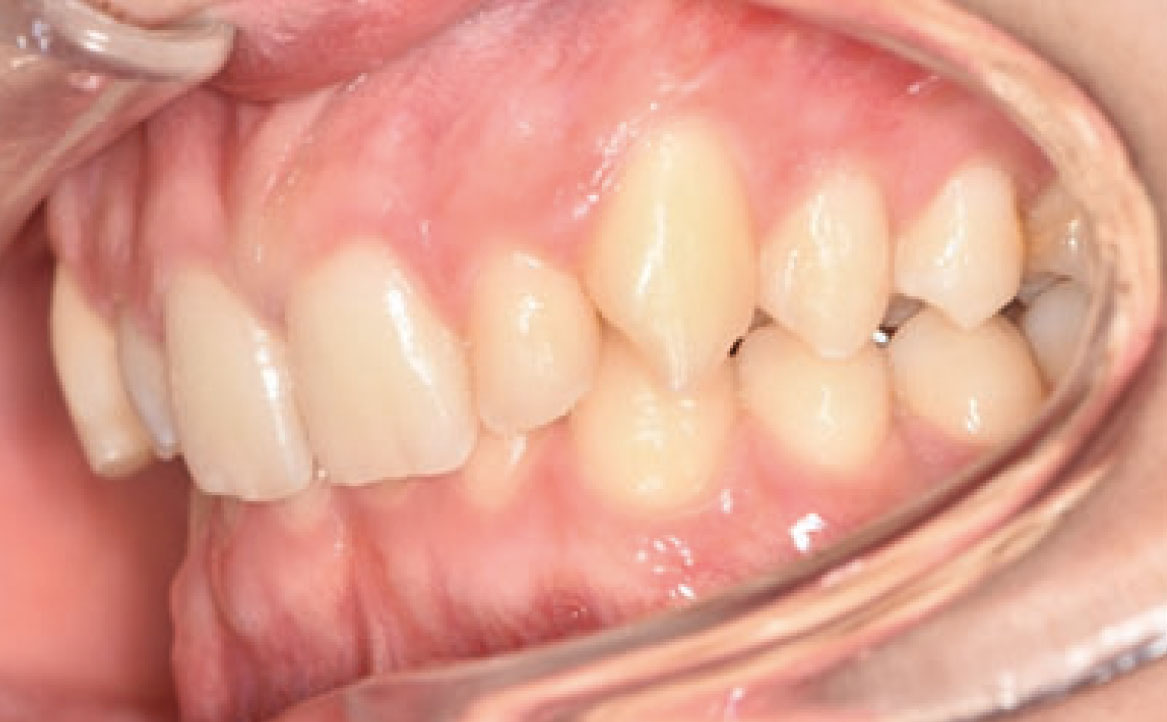

Il paziente si è presentato per la sua prima visita presso il reparto di Odontoiatria e Protesi Dentaria dell’Ospedale Vita-Salute San Raffaele diretto dal prof. E. F. Gherlone. All’esame obiettivo era evidente una malocclusione scheletrica e dentale di classe II associata a morso profondo e lieve affollamento anteriore superiore. In particolare, sono stati segnalati: rapporti occlusali di classe II, morso profondo, perdita di overjet, contrazione dell’arcata superiore e inferiore con leggero affollamento (fig. 1a-f). La richiesta del paziente era quella di migliorare l’estetica dei denti anteriori con allineatori invisibili di tipo Invisalign. Tuttavia, sia il paziente che il genitore sono stati informati che, per ragioni di efficacia e risoluzione del problema, era necessario agire anche a livello di funzionalità e risoluzione della malocclusione.

In primo luogo, sono stati prescritti entrambi gli esami radiografici ortodontici: OPT e teleradiografia latero-laterale del cranio (fig. 2a-b). Successivamente, in accordo con il genitore, è stata concordata una terapia ortodontica in due tempi. L’inizio della terapia è stato effettuato con Carriere Motion ed elastici di classe II, con l’obiettivo di migliorare la classe molare (fig. 2c-e).

Infatti, durante il primo controllo due mesi dopo, è stato osservato un miglioramento della classe molare (fig. 3a-c).